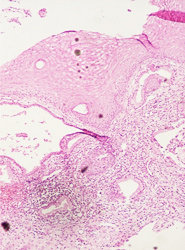

El resultado de una valoración colposcópica de paciente con lesión displásica siempre será confirmado por el estudio histopatológico que realiza el médico anatomopatólogo (estudio de la biopsia tomada en la colposcopía) . A continuación presentamos imágenes histológicas con sus diagnósticos.

• NIC 1 (Displasia leve de cérvix)

• NIC I.- Acantosis regular, anisocitosis y anisocariosis leves. Proceso inflamatorio en la lámina propia severo reactivo.

• NIC I.- Anisocitosis y anisocariosis leves. Estroma ricamente vascularizado.